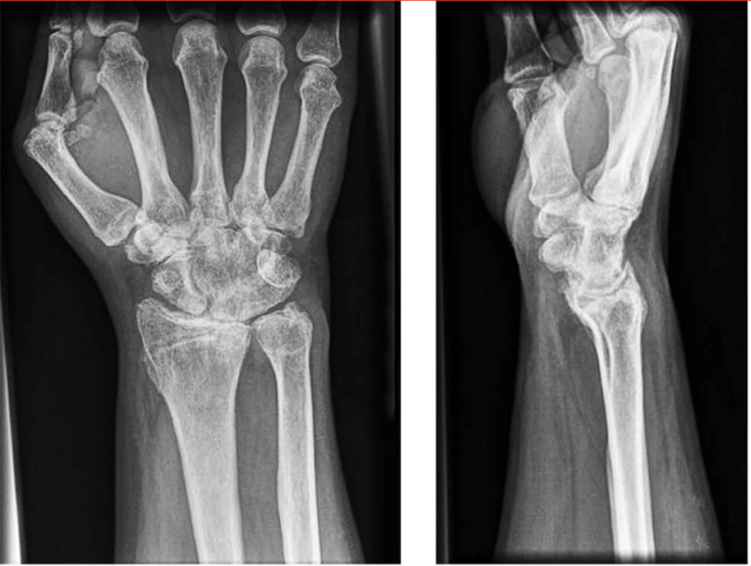

X-ray Showing Wrist Arthritis

X-rays of a patient with wrist arthritis. On these images, there is clearly severe cartilage wear causing narrowing of the joints of the wrist.

Adapted with permission from Wei DH, Feldon P. Total Wrist Arthrodesis: Indications and Clinical Outcomes. J Am Acad Orthop Surg. 2017;25(1):3-11. doi:10.5435/JAAOS-D-15-00424